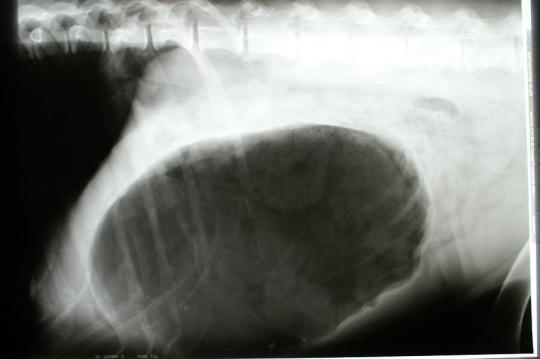

Alle Vorzeichen deuten auf eine Magendrehung hin. Als Sofortmassnahme wird deshalb zur Kreislaufstützung eine intravenöse Infusion in Schockdosis verabreicht. Währenddessen wird zur Diagnosesicherung in Seitenlage eine Röntgenaufnahme des Bauches angefertigt. Diese zeigt das klassische „Zipfelmützenbild“ eines aufgegasten und teilweise rotierten Magens.